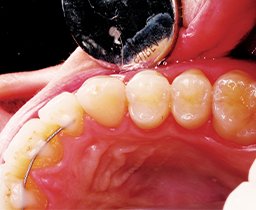

The contact was broken bucco-lingually and gingivally with the fender wedge in place (Fig. 3). The fender wedge was removed in order to evaluate the prep (Fig. 4).

Fig. 4 Fig. 5

The tooth was restored using a sectional matrix system in about six minutes (Fig. 5).